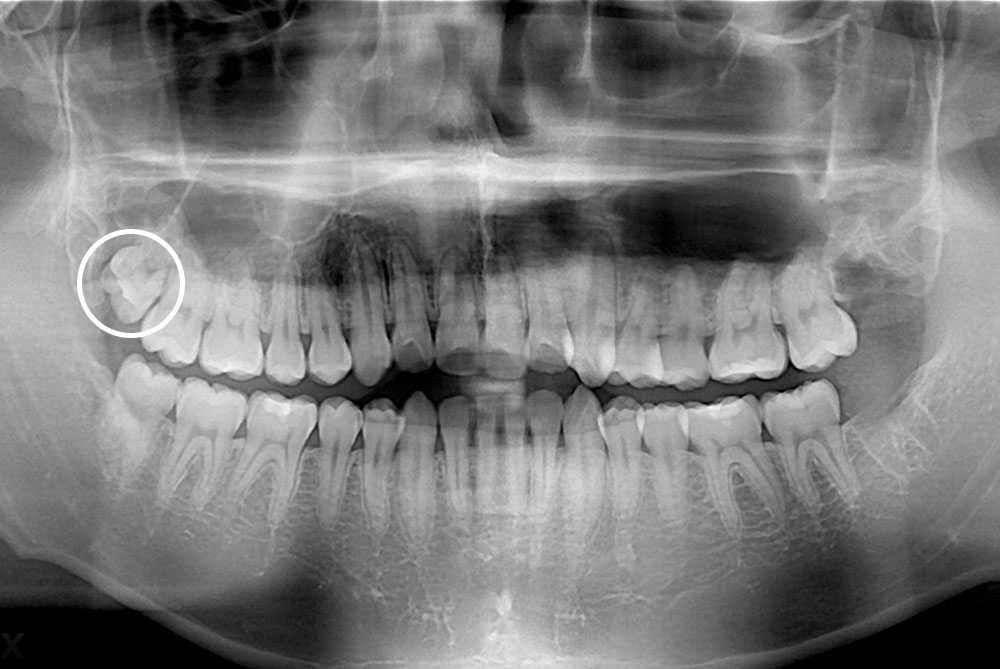

[사랑니] 매복 사랑니 발치

치료후 : 2019-02-11

세종치과는 구강악안면외과학 박사이신 원장님이 발치하는 치과입니다.